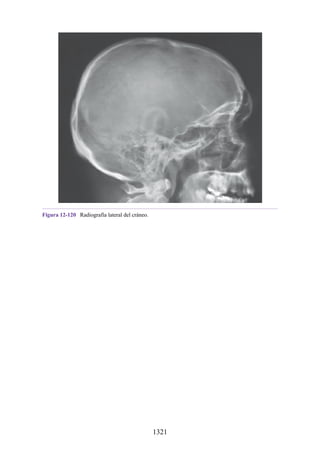

cuádriceps femoral, de antagonista durante la flexión de la rodilla.

Fijador: un músculo fijador se contrae isométricamente (p. ej., la contracción